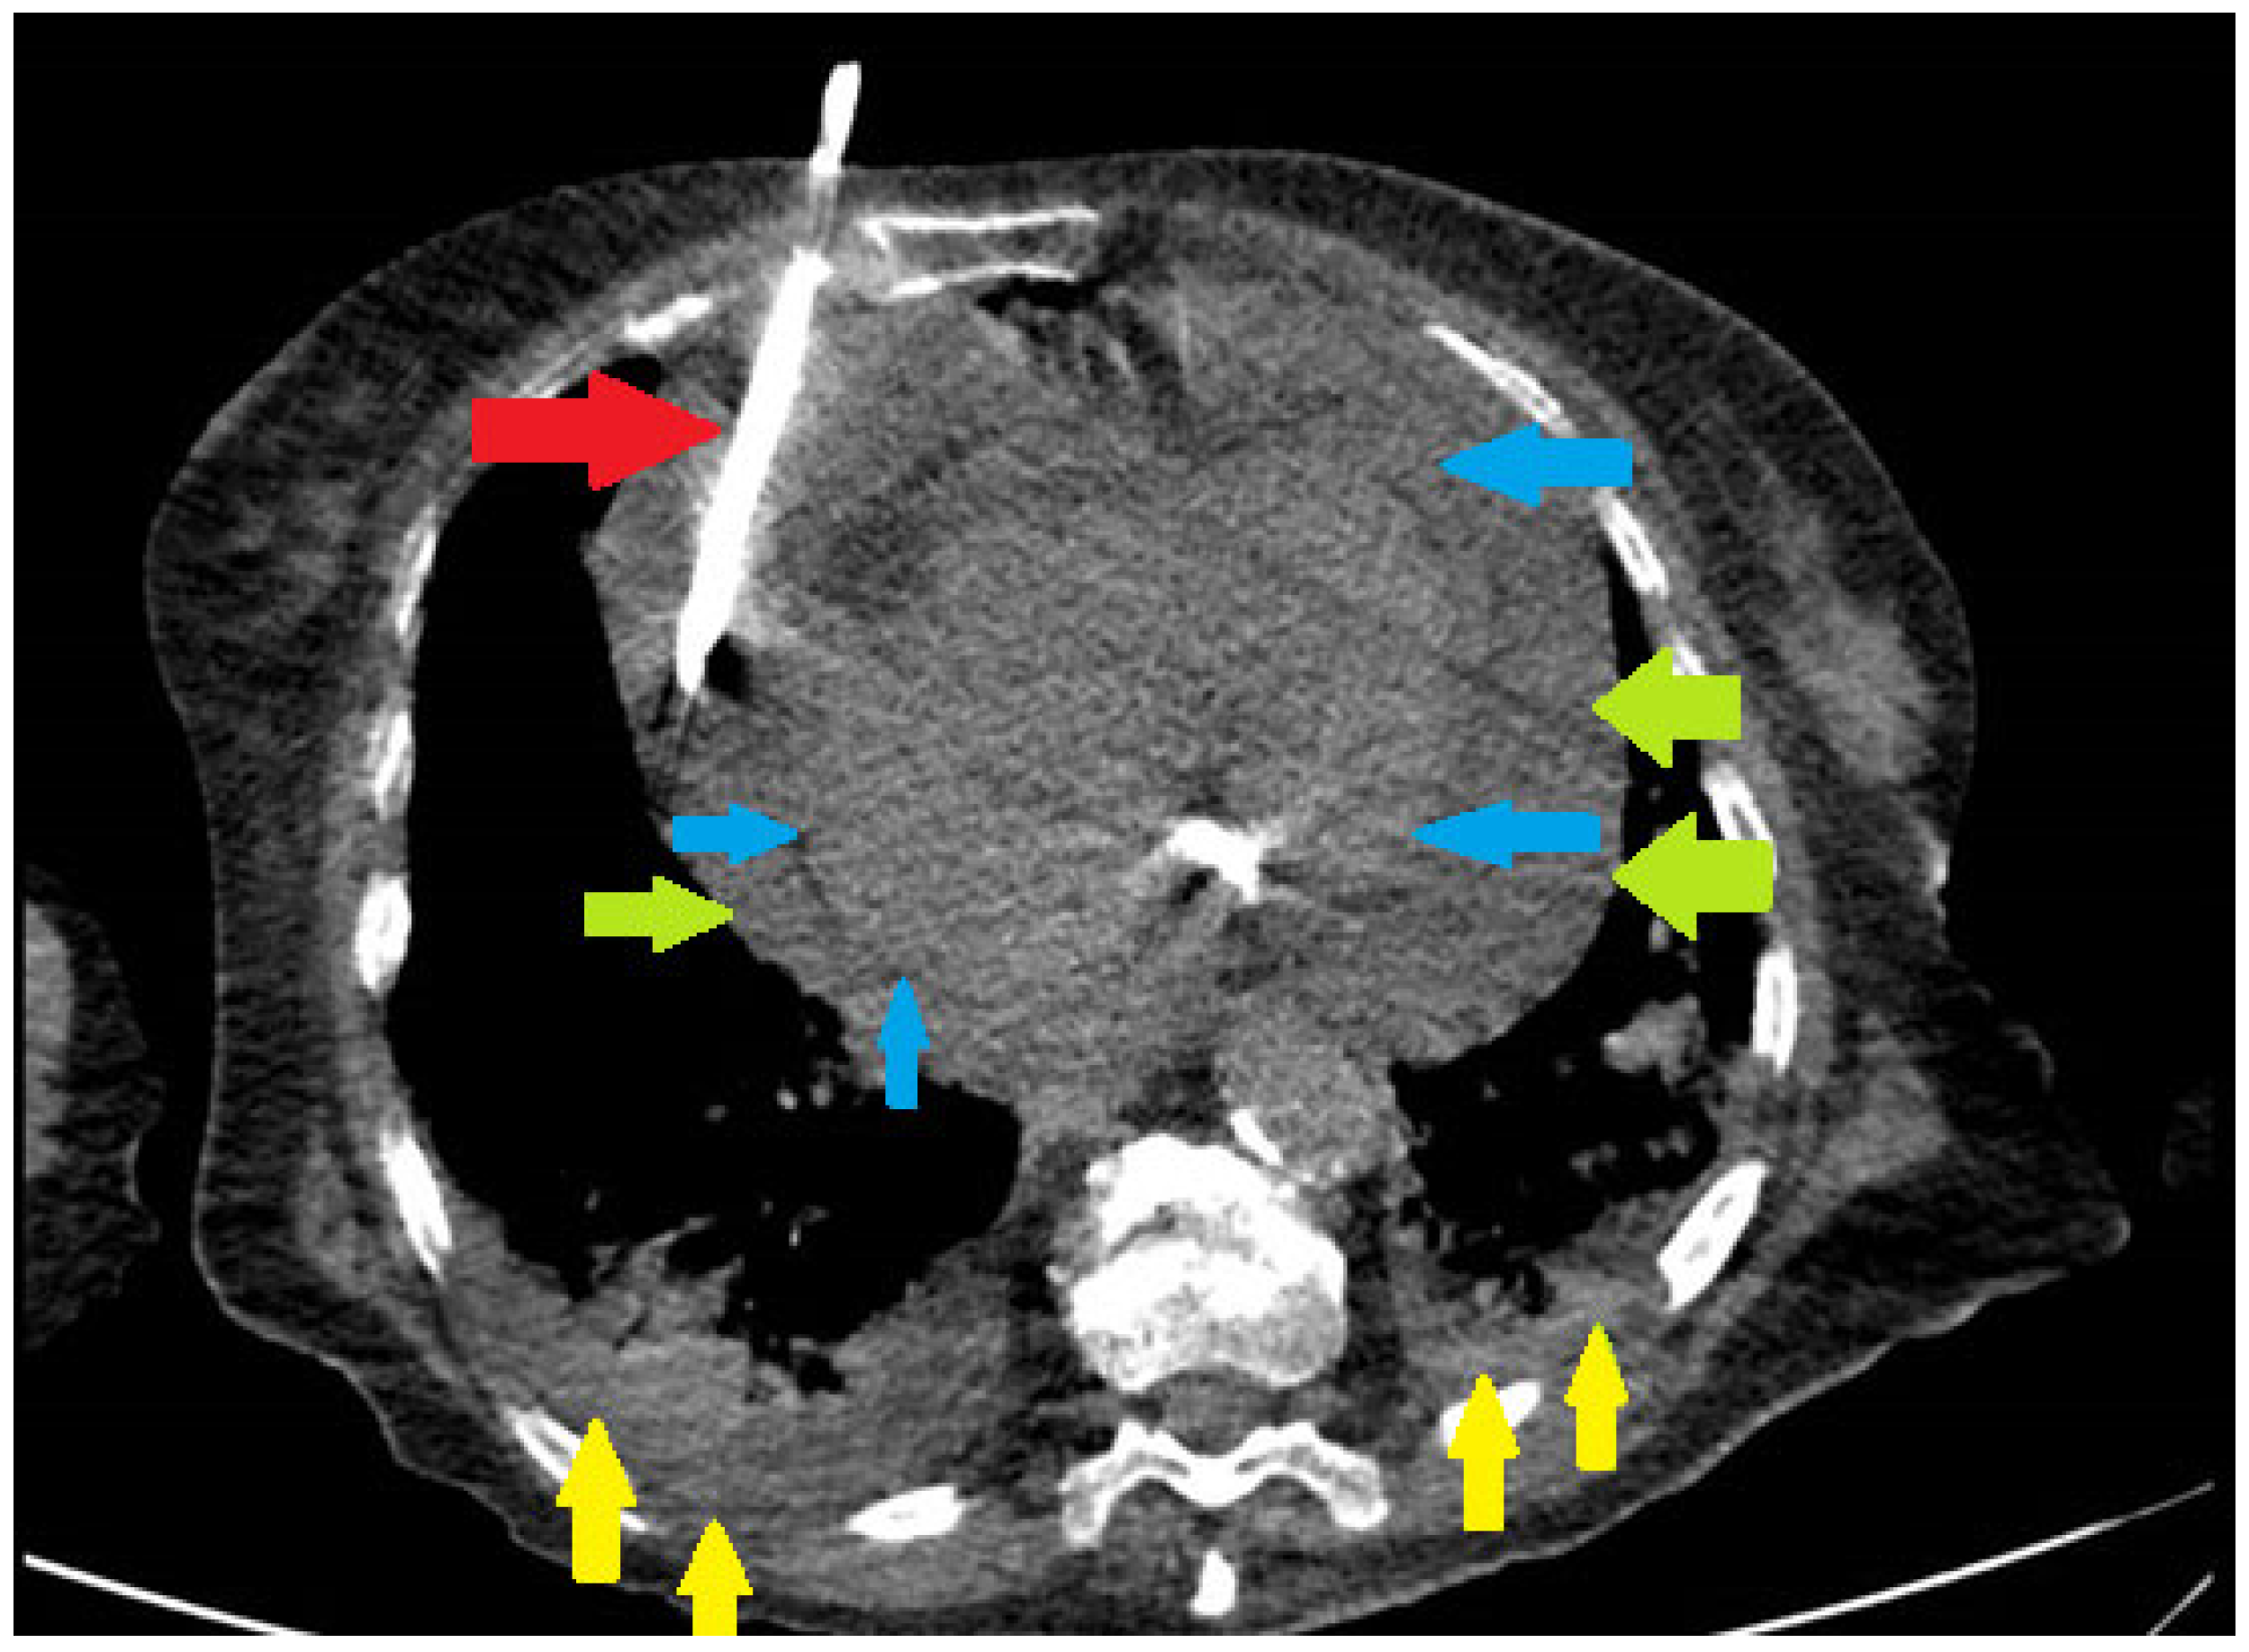

Pericardiocentesis was defined as needle aspiration of pericardial fluid or any surgical procedure involving drainage of pericardial fluid, including surgical pericardiotomy and pericardial window (Figure 1). Patient records with ICD code of pericardiocentesis, pericardiotomy or pericardiectomy were thoroughly reviewed by the investigators, to ensure that drainage of pericardial fluid was performed.

Pericardial drain insertion in a patient with COVID-19 infection, large pericardial effusion, and bilateral pneumonia. Red arrow—pericardial drain. Green arrows—parietal pericardium. Blue arrows—visceral pericardium. Yellow arrows—pulmonary infiltrate.